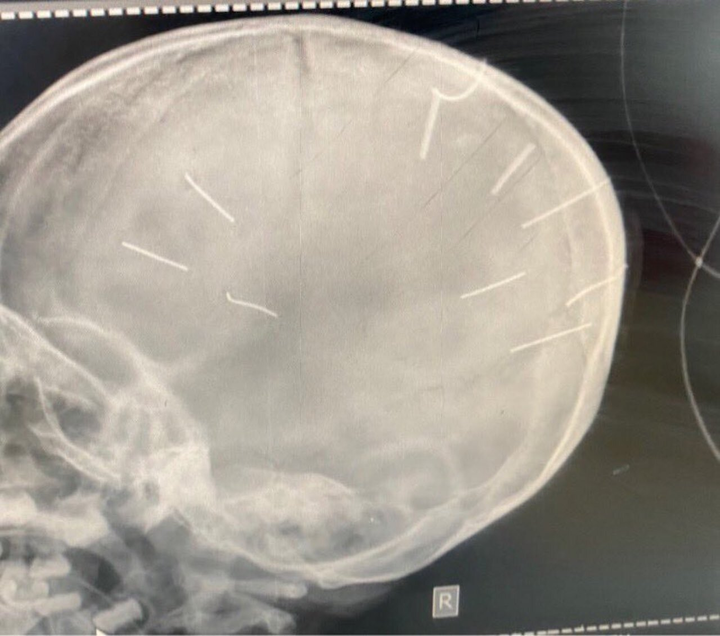

Hình ảnh phim chụp X-quang cho thấy hộp sọ của bệnh nhi có 9 đinh. (Ảnh: BVCC)

Trước đó, Bệnh viện Đa khoa huyện Thạch Thất tiếp nhận bé Đ.N.A. trong tình trạng nguy kịch, phim chụp X-quang cho thấy có đinh trong sọ, tiên lượng tử vong cao.

Bệnh nhi được đặt ống, chụp phim chẩn đoán. Kết quả hộp sọ bé có hình ảnh cản quang. Bệnh nhi được chẩn đoán sơ bộ hôn mê nghi viêm màng não. “Do tình trạng bệnh diễn tiến nặng, kèm với dấu hiệu bất thường, chúng tôi đã chuyển bệnh nhi lên tuyến trên là Bệnh viện Đa khoa Xanh Pôn, đồng thời báo cho công an huyện Thạch Thất”, BS Kiên nói.

Đáng chú ý, tại Bệnh viện Đa khoa Xanh Pôn, kết quả phim chụp cắt lớp cho thấy bệnh nhi Đ.N.A. có hình ảnh như bị đinh bắn vào hộp sọ. “Có 9 chiếc đinh. Bệnh nhân đang trong tình trạng rất nặng, đe doạ tử vong cao”, BS Kiên cho biết thêm.